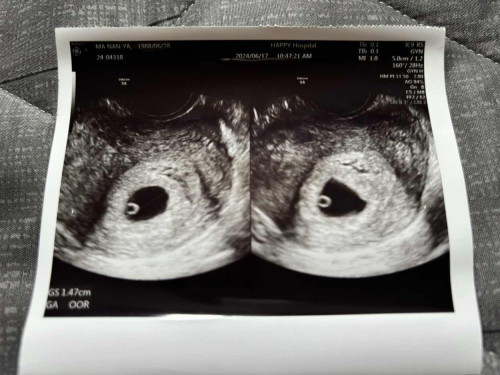

วันนี้ไปหาคุณหมอมา หมอบอกว่าน้องน่าจะได้ 4-5 week แต่ถ้าเรานับตามรอบเดือนครั้งสุดท้าย 4 พค น้องน่าจะได้ 6 week แล้วค่ะ

แล้วซาวน์มาเจอแบบนี้ คือเจอแต่ถุงตั้งครรภ์กับถุงไข่แดงของน้องใช่ไหมค่ะ ยังไม่เจอน้องใช่ไหม เรามีกังวลนิดนึงค่ะตอนนี้ พอดีเราอยู่ต่างประเทศ สื่อสารกับคุณหมอไม่ค่อยเข้าใจ ใครพอดูผลเป็น ช่วยหน่อยค่ะ

เหมือนของเราเลยค่ะ เราตรวจอัลตาซาวผ่านช่องคลอด ตอนนี้ 5w5dคุณหมอบอกว่าดีใจด้วยนะคะ ตั้งครรภ์ในมดลูก มีถุงตั้งครรภ์ และมีไข่แดงสมบูรณ์เราตรวจที่ รพ รามาธิบดีค่ะ จ่กที่หาข้อมูลมา เจ้าไข่แดงจะพัฒนาเป็นตัวอ่อนต่อไปค่ะ อายุครรภ์ต้องมากกว่านี้หน่อยถึงจะซาวเจอตัวอ่อนค่ะ

บ้านนี้6สัปดาห์ค่ะไปตรวจเมื่อเจอน้องแล้วนะคะหมอบอกว่าถ้าไม่เจอน้องก็ไม่ต้องตกใจเพราะอาจจะอายุครรภ์น้อยเกินไปเลยยังทำให้ไม่พบน้องค่ะ คุณแม่ไม่ต้องตกใจน๊า

เหมือนกันเลยไปซาว 6w เจอถุง กับไข่แดง รอซาวอีกที 8-9w น่าจะเจอน้องค่ะ หวังว่าจะเจอน้องน้า🥺🥺🥺🥺

เหมือนกันค่ะตอนนั้นซาวด์ตอน6wเจอเเต่ถุงไข่เเต่พอไปซาวด์ตอน7wก็เจอตัวน้องค่ะ

ถ้าเห็นแบบนี้คือมีหวังนะคะคุณแม่